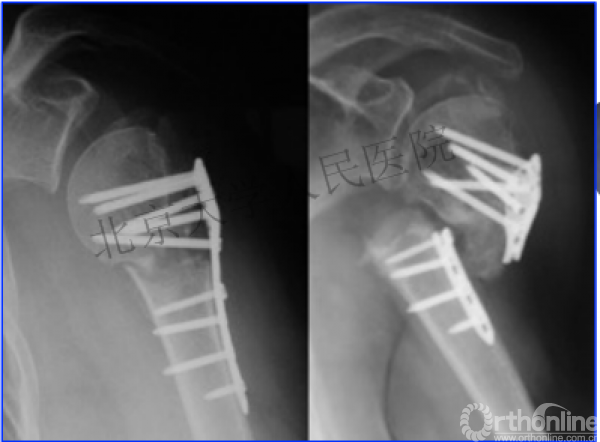

内侧皮质粉碎,低位外科颈骨折,肱骨头-干角维持困难。

术后复位丢失,肱骨头内翻畸形。

能否该偏心固定(钢板)为髓内固定,增加力臂?

早知今日,何必当初?

此时对比髓内钉是不是有很大优势?